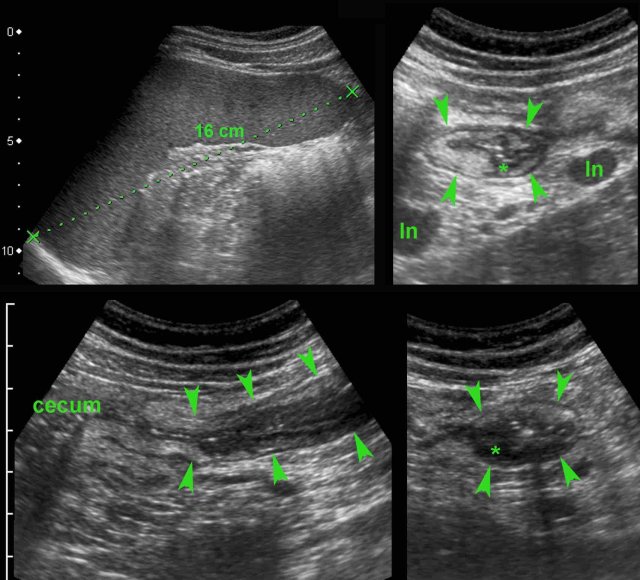

This Dutch student  presented with high fever, constipation and RLQ  pain after returning from India.

US showed splenomegaly and wall thickening of the terminal ileum (arrowheads) with evident hypoechoic transmural changes (*).

There was also inflamed fat around the ileum and the mesenteric lymph nodes (ln) were enlarged.

Two days later, blood cultures were positive for Salmonella typhi.

Complete recovery with antibiotics.

S. typhi is the only bacteria that shows this invasive behavior and may very closely mimic the US features of Crohn’s disease.